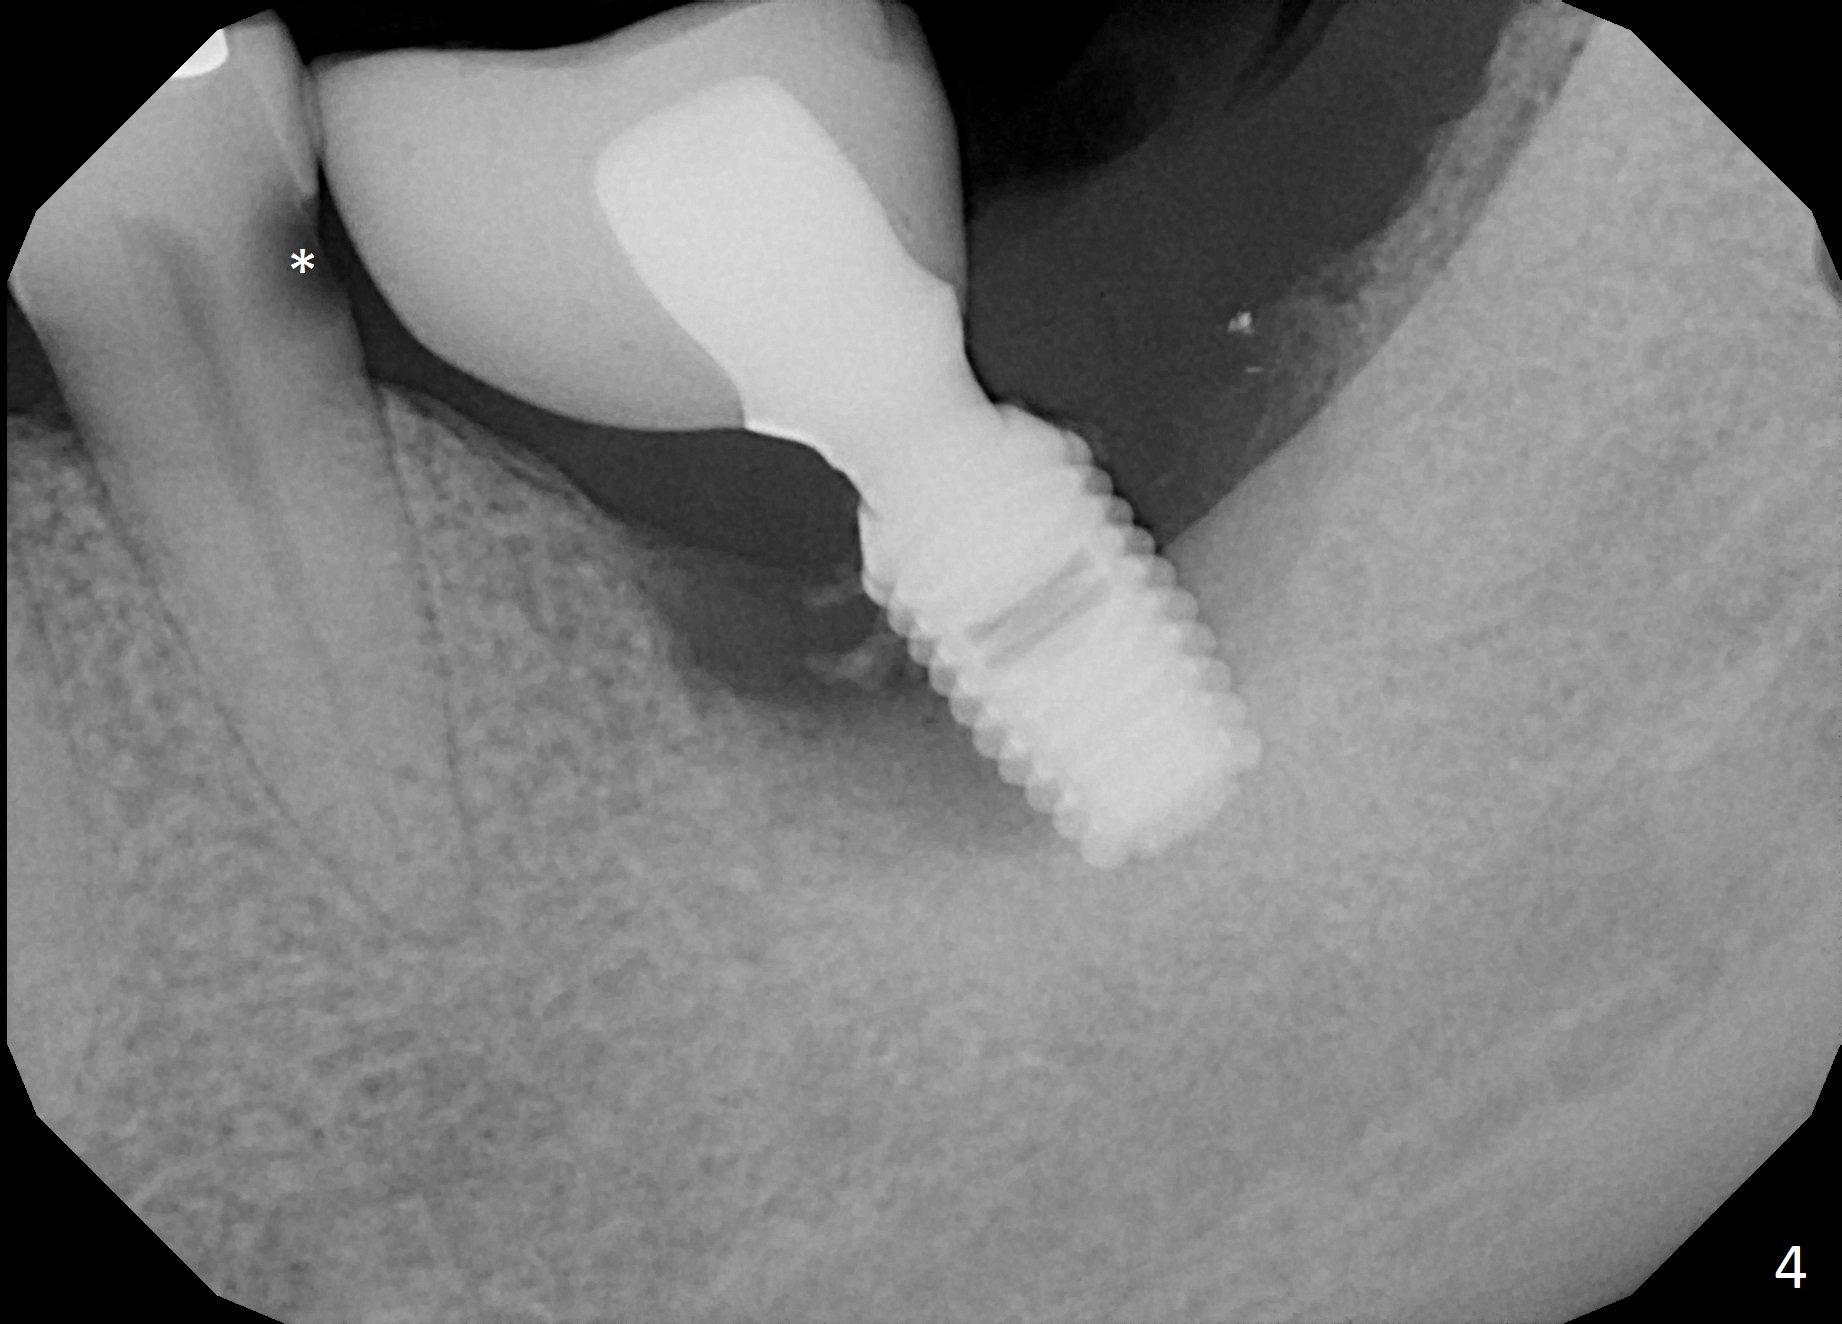

A 42-year-old woman presented to clinic 11 years ago with history of extraction of the tooth #19 two months earlier (Fig.1).  Two months later, a 5x8 mm Bicon implant was placed (Fig.2).  Integrated Abutment Crown was delivered 2 years later (Fig.3) with persistent radiolucency in the mesial socket.  The tooth #18 was extracted with socket preservation 7 years ago.  Recently she returned with chief complaint of chewing pain in the lower left for a while.  The buccal gingiva of #19 is erythematous, edematous and tender (Fig.4).  There are healing abutment at #29 and implant crown at #30.

Periimplantitis at #19 is most likely due to buccodistal placement.  When it is removed (Clindamycin), a smaller IBS or SM implant will be placed immediately and mesiolingually (Fig.3).  For better wound protection with periodontal dressing or provisional, an implant will be placed at #18 at the same appointment.  Draw blood for PRF if the vein is large enough.  Surgical stents have been in cold sterilant.